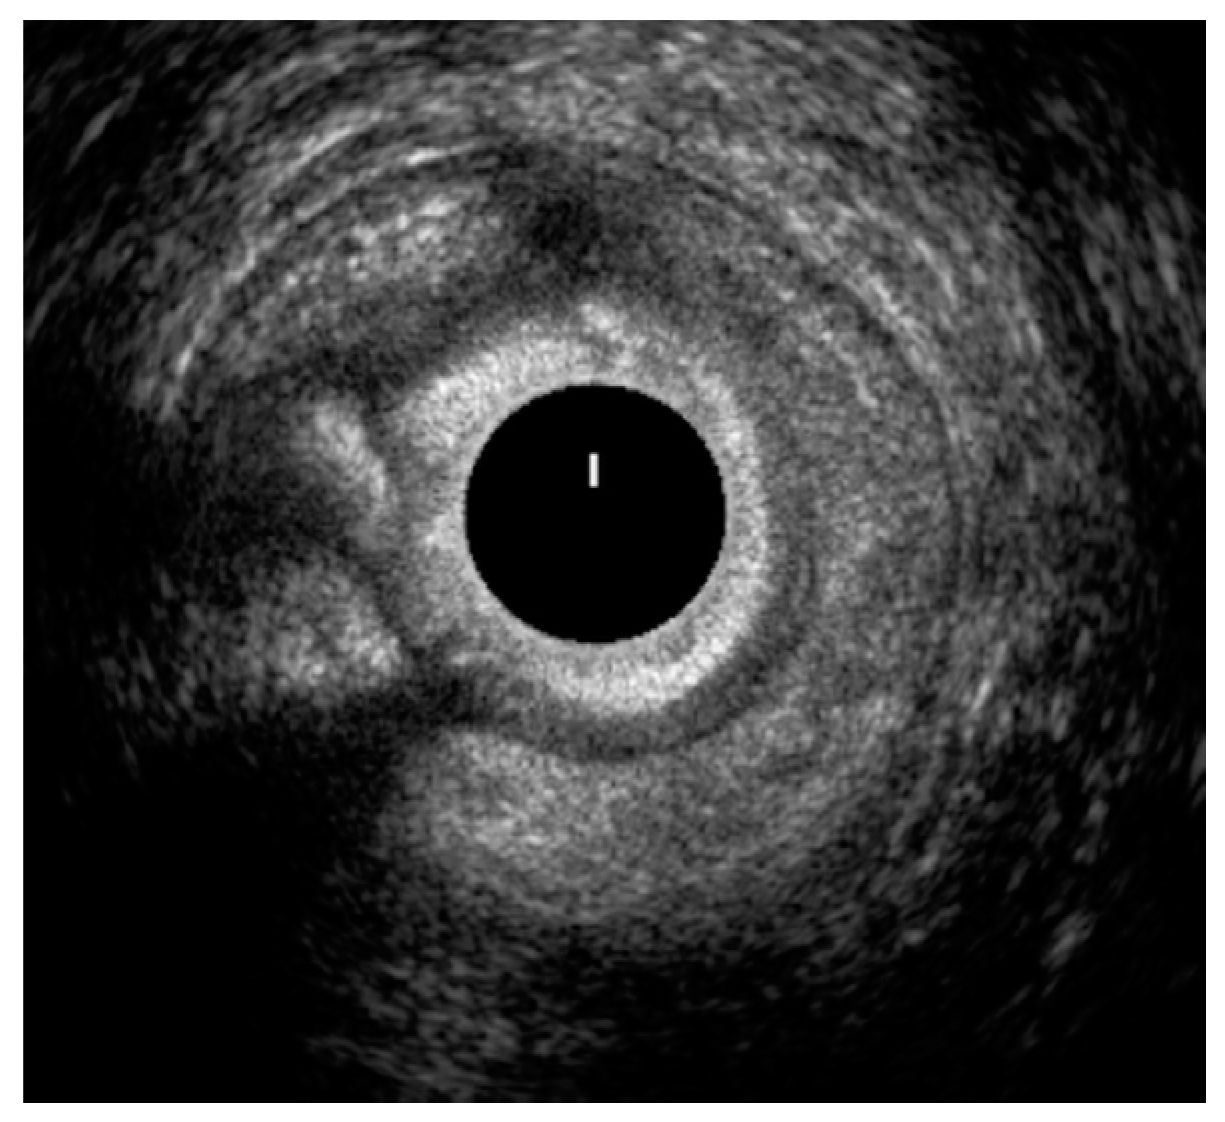

3.3. High-Resolution Anorectal Manometry and Balloon Expulsion Test